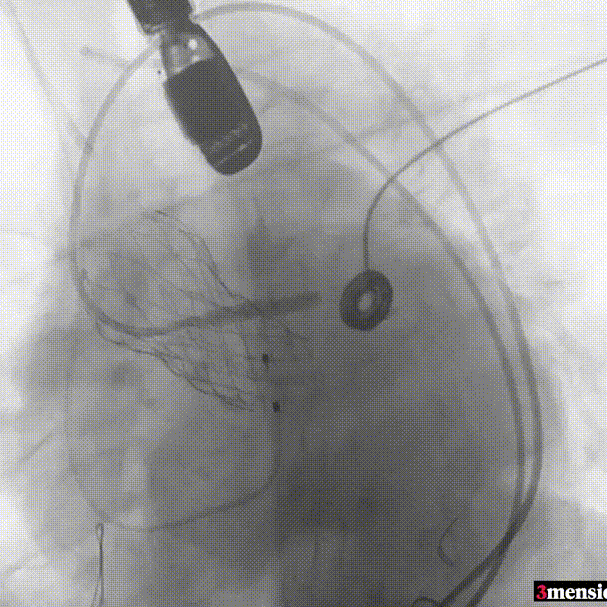

手术过程回顾:

患者全麻后,右侧股动脉建立主入路,主动脉根部造影显示主动脉瓣无明显钙化。心室内轻中量反流,主动脉及心脏情况整体较为稳定,根据术前策略预装23mm瓣膜。超硬置入左心室后,因超硬压迫无冠瓣叶导致急性反流,病人血压降至40mmHg,遂迅速将输送器送入主动脉根部,快速释放瓣膜后,病人血压恢复至正常。瓣膜脱钩后造影显示左冠开口存在一定狭窄,IVUS评估左冠开口狭窄约60%,符合PCI指征,植入开窗支架改善狭窄,最终再次造影加IVUS评估左冠开口,确定狭窄解除。

IVUS探查左冠开口狭窄60%

放置开窗支架

球囊后扩支架

假体瓣膜形态良好,无明显瓣周漏

术后测量跨瓣压差仅为1mmHg